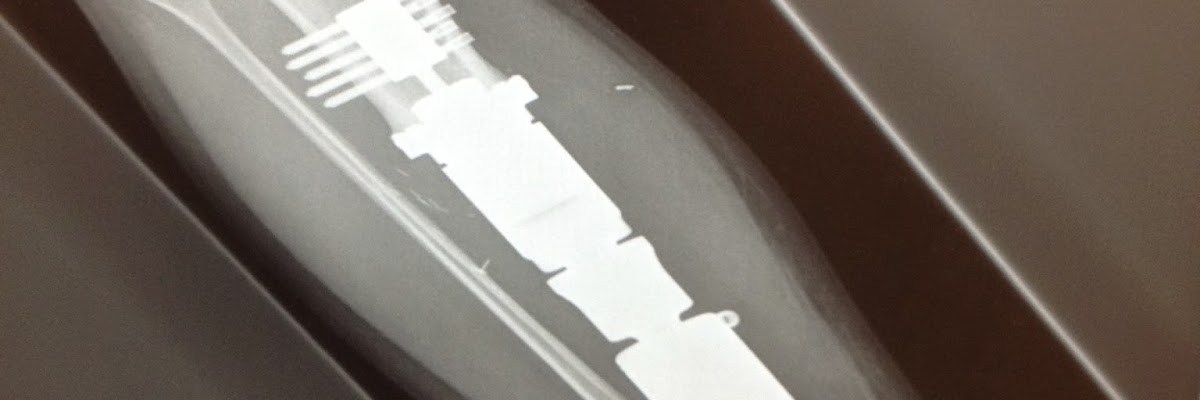

| Greg’s leg today |

Today we celebrate the FIVE year anniversary of Greg’s surgery in which 10 inches of tibia was removed and replaced with a prosthetic implant. It was a lifetime ago, and yet happened only yesterday!